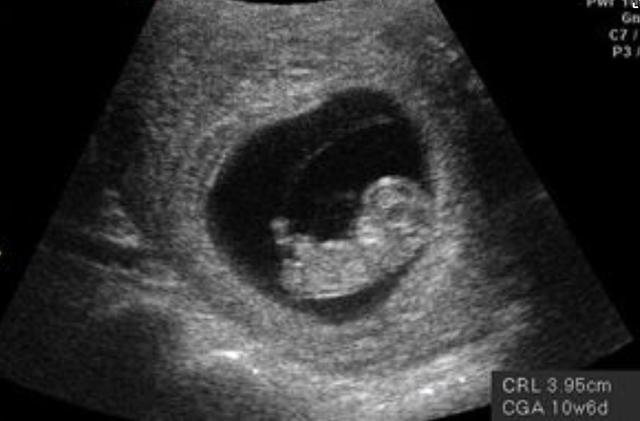

1、怀孕3个月

在前3个月时,尽管胎儿在妈妈的肚子里动来动去,但是孕妇一般是感觉不到的。到了3个月之后,孕妇的身材会有些明显变化了,肚子能看到隆起的样子了,因为这时候胎儿已经长大了。通常,3个月大的胎儿为15g左右,身长就是10cm左右,如小手掌般大,所以,这时候的孕肚还不会给孕妇的生活带来很大的影响。